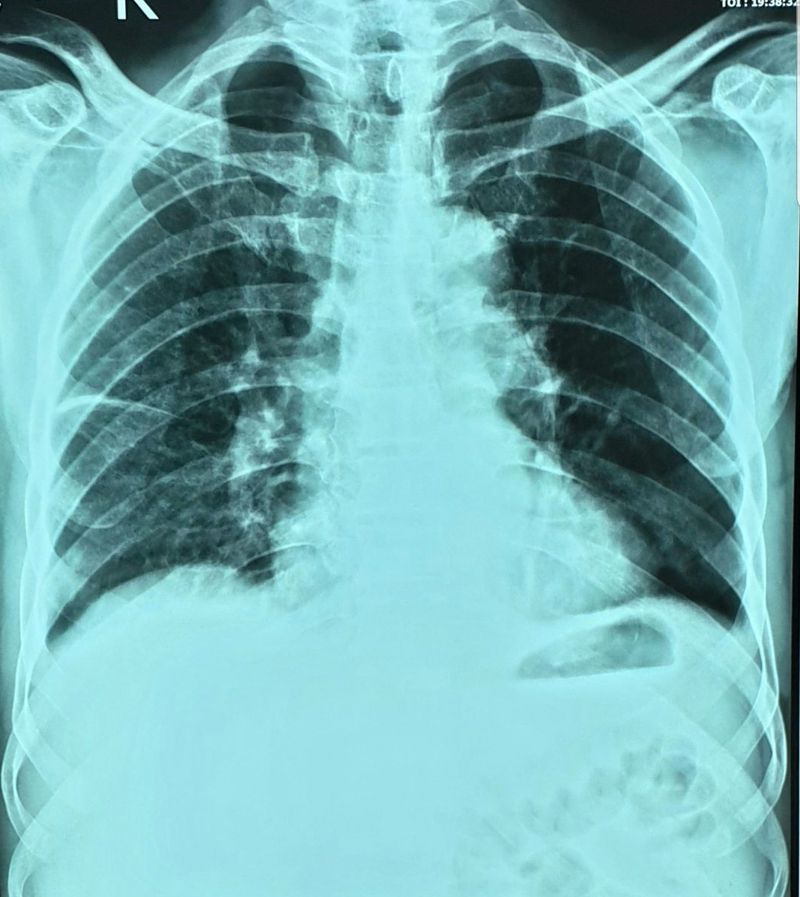

A 65 year old man with fever

It si not a really good X ray because it si overexpoused and rotated to the left side. But it seems to be some kind of liquid collection no the right cisure. Also the nodes on the right hillium are big. Could be cancer??

HRCT Chest was done which showed no nodal enlargement.